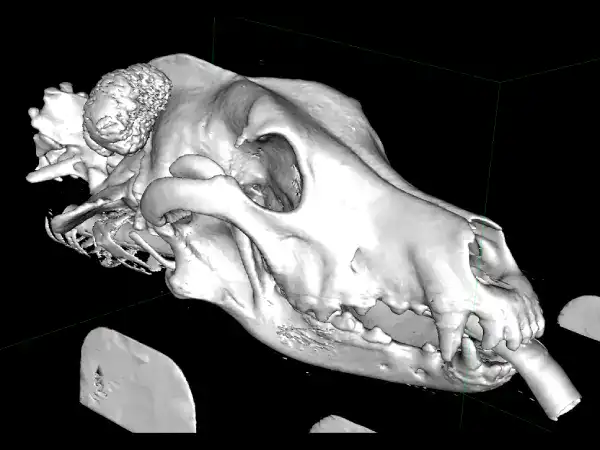

Beau, a 7-year-old male neutered German Shepherd, was referred to us in June 2025 for investigation and treatment of a slow-growing mass on the back of his skull.

CT confirmed an osteoproliferative mass originating from the nuchal crest, the appearance of which was typical for multilobular tumour of bone, also known as a multilobular osteochondrosarcoma (MLO). The histopathological diagnosis of MLO was confirmed with a minimally invasive biopsy.